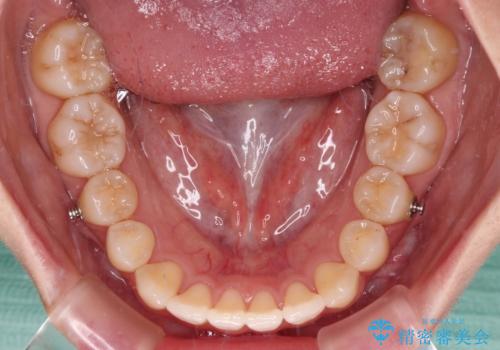

- 上顎前歯の隙間を気にして来院された患者様です。

下顎前歯が上顎前歯に食い込むような咬み合わせにより、上顎前歯が開いてしまっていたため、咬合高径の挙上により突き上げを改善するよう、インビザラインにより矯正治療を行うこととしました。

咬合高径の挙上により上顎前歯の突出感も改善することができ、整った口元となりました。